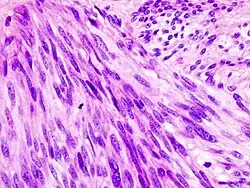

![]() | |

Histopathologic image of gastrointestinal stromal tumor of the stomach. Hematoxylin-eosin stain. | |

The definitive diagnosis is made with a biopsy, which can be obtained endoscopically, percutaneously with CT or ultrasound guidance or at the time of surgery. A biopsy sample will be investigated under the microscope by a pathologist physician. The pathologist examines the histopathology to identify the characteristics of GISTs (spindle cells in 70-80%, epitheloid aspect in 20-30%). Smaller tumors can usually be confined to the muscularis propria layer of the intestinal wall. Large ones grow, mainly outward, from the bowel wall until the point where they outstrip their blood supply and necrose (die) on the inside, forming a cavity that may eventually come to communicate with the bowel lumen.

When GIST is suspected—as opposed to other causes for similar tumors—the pathologist can use immunohistochemistry (specific antibodies that stain the molecule CD117 [also known as c-KIT] —see below). 95% of all GISTs are CD117-positive (other possible markers include CD34, Discovered On GIST-1 (DOG1),[19] desmin, and vimentin). Other cells that show CD117 positivity are mast cells.